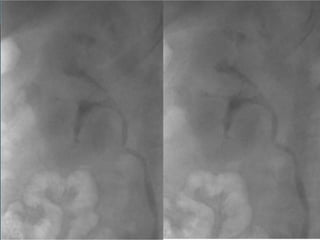

• #40 NEOPLASIA UROTELIAL PIELOCALICIAL DERECHA. La UIV muestra defecto de repleción pièlico irregular que se extiende a grupo caliacial superior.

• #41 NEOPLASIA UROTELIAL PIELOCALICIAL DERECHA. El estudio axial por TC demuestra el defecto de repleción piélico irregular que se extiende a grupo calicial superior correspondiente a la neoproliferación.